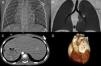

Os autores descrevem os achados em TC de uma criança do sexo masculino com 29 meses, referenciada para angio-TC cardíaca para avaliação de uma cardiopatia congénita complexa. O estudo foi efetuado em equipamento multi-corte de dupla-ampola de 128 cortes (Siemens Definition Flash) com sincronização electrocardiográfica prospetiva, que demonstrou mesocardia com situs inversus abdomino-auricular (Figura 1), discordância aurículo-ventricular e ventrículo-arterial com comunicação interventricular subpulmonar e artéria coronária única (Figura 2). A dose de radiação efetiva foi de 1,0mSv (DLP 25mGy*cm).

Discordância aurículo-ventricular e ventrículo-arterial e artéria coronária única. (A) Imagem axial e (B, C e D) reconstruções multiplanares evidenciando discordância aurículo-ventricular e ventrículo-arterial, com aorta anterior e direita e artéria pulmonar posterior e esquerda, defeito do septo infundibular com comunicação interventricular subarterial (*), bem como origem anómala da artéria coronária direita do seio coronário esquerdo, com trajeto entre a aorta e a artéria pulmonar.

AD: aurícula direita; AE: aurícula esquerda; Ao: artéria aorta; CD: artéria coronária direta; Cx: artéria circunflexa; DA: artéria descendente anterior; P: artéria pulmonar; VD: ventrículo direito; VE: ventrículo esquerdo.